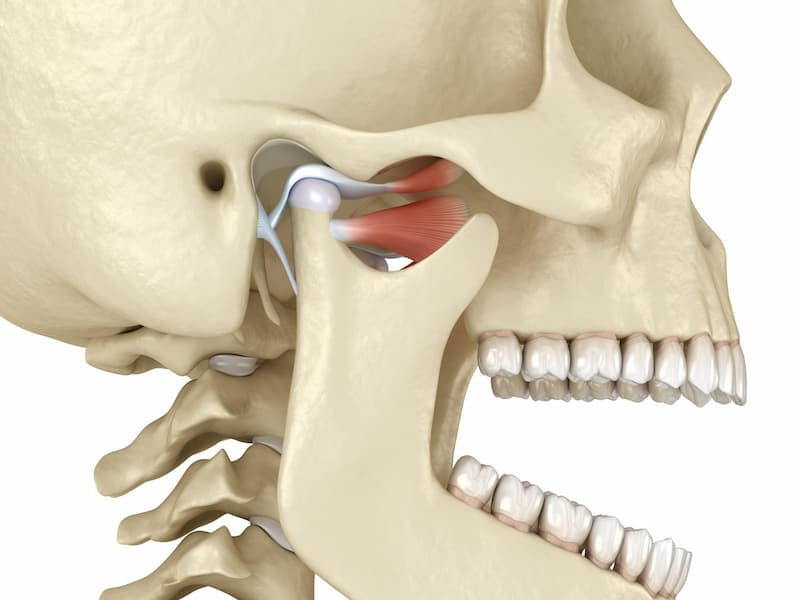

مشخصات ایمپلنت فک کامل

ایمپلنت فک کامل، راهی عالی برای جایگزین کردن دندانهای گمشده است و باعث تقویت قوس های فکی و بهبود خط بندی نیز میشود.